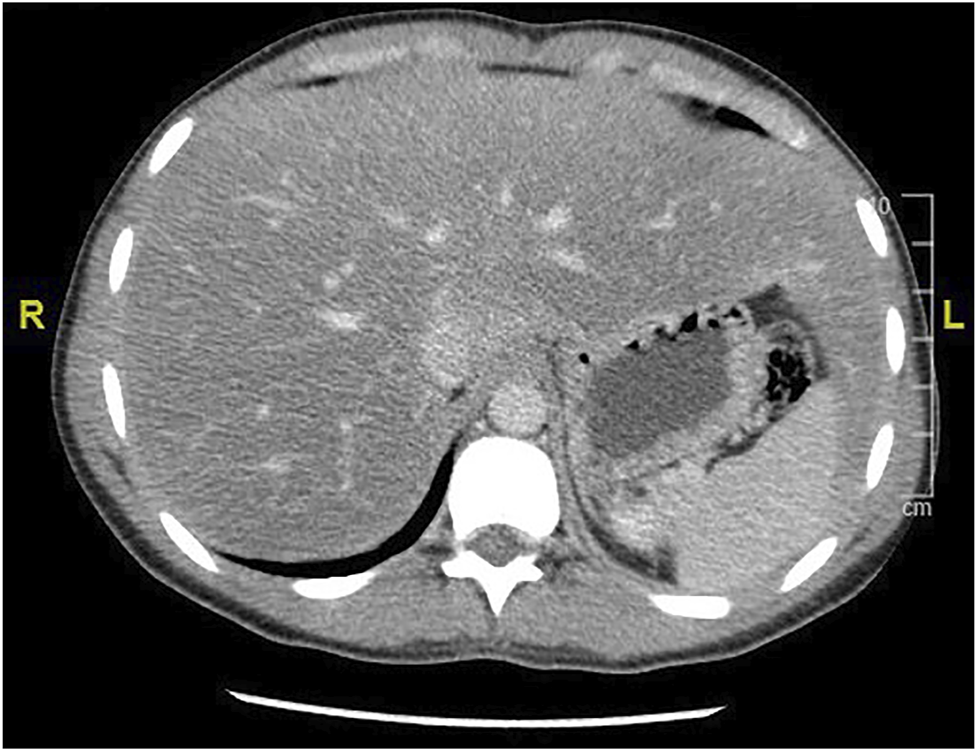

GlyH and hepatic steatosis showcase important similarities on ultrasound imaging studies. Ultrasound studies will reveal hyperechogenic liver parenchyma and hepatomegaly, mimicking NAFLD (Figure 2). Moreover, criteria to define echogenicity or liver size are subjective and often ill-defined. Computed tomography (CT) could aid to differentiate between GlyH and NAFLD, since GlyH features an increased liver density on CT, whereas liver density is decreased in patients with NAFLD, especially compared to the density of the spleen (Figure 3) (Sweetser and Kraichely, 2010). However, CT diagnosis of NAFLD is not recommended in guidelines, nor studied in T1D cohorts, so the utility of CT needs further validation, especially due to the radiation burden associated with CT, which is not present in MRI-based imaging (see Table 2) (Marchesini et al., 2016; Chalasani et al., 2018; de Vries et al., 2020). Furthermore, as mentioned above, and in Table 1, steatosis is often co-present in GlyH and vice versa, potentially attenuating the contrast on CT and impeding diagnosis. Neither CT nor ultrasound are thus useful tests for the definitive diagnosis of GlyH. However, MRI-based imaging studies might be beneficial, since MRI can distinguish fat from glycogen deposition or acute tissue injury. MRI imaging in GlyH shows low intensities on T2 weighted images, whereas T1 weighted gradient-dual-echo MRI images with in-phase and opposed-phase conditions could efficiently differentiate hepatic glycogen from liver steatosis (Table 2 and Figure 4) (Sweetser and Kraichely, 2010; Saikusa et al., 2013).

FIGURE 3. CT imaging features of liver steatosis. Caption: Transverse CT image of the liver showing decreased density of the liver compared to the spleen in this 38-year old patient with NAFLD. In GlyH, the inverse image can be witnessed with increased density compared to the spleen, but due to concomitant steatosis, this contrast is potentially attenuated in metabolic patients.